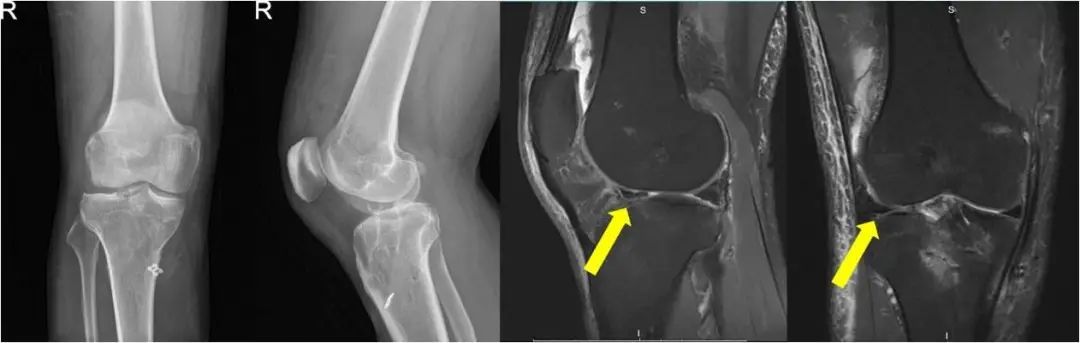

术后影像学显示移植半月板已填充在正常位置,匹配良好